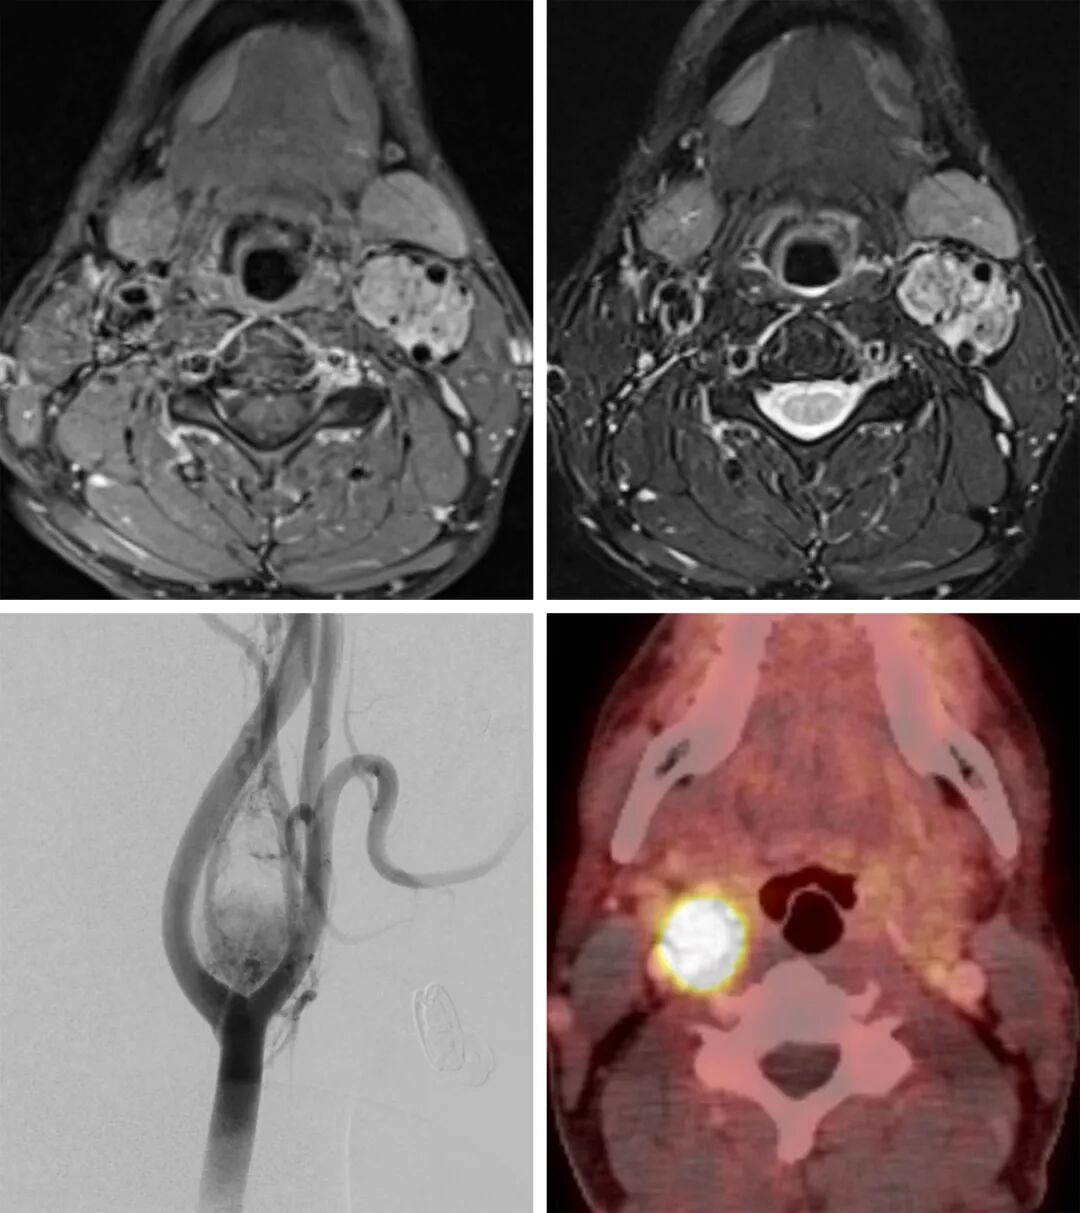

图2. 这一个诊断为多发副神经节瘤的患者,T1FS 增强相(左上)及T2FS相(右上)提示肿块强化明显并延伸至左颈内动脉及颈外动脉,同时伴有血管流空现象。DSA提示血供丰富的肿块蔓延至左颈内及颈外动脉(左下图)。经栓塞后,通过68Ga-DOTANOC PET/CT检查病变位置的变化情况。68Ga-DOTANOC存在于表达生长抑素特异性受体的器官及肿瘤。右下图提示肿块位于左颈动脉间隙中,并有68Ga-DOTANOC高度强化,符合颈动脉体副神经节瘤的诊断。

123I-间碘苄胍:放射药剂主要集中于分泌儿茶酚胺的肿瘤,副神经节瘤的敏感度为57%-78%。

111I-奥曲肽:放射药剂主要集中于能够表达生长抑素受体的肿瘤,副神经节瘤的敏感度为94%。

68Ga-DOTANOC与68Ga-DOTANOC PET/CT:新型PET/CT诊断用于检测表达生长抑素受体的肿瘤(神经内分泌瘤、副神经节瘤等)